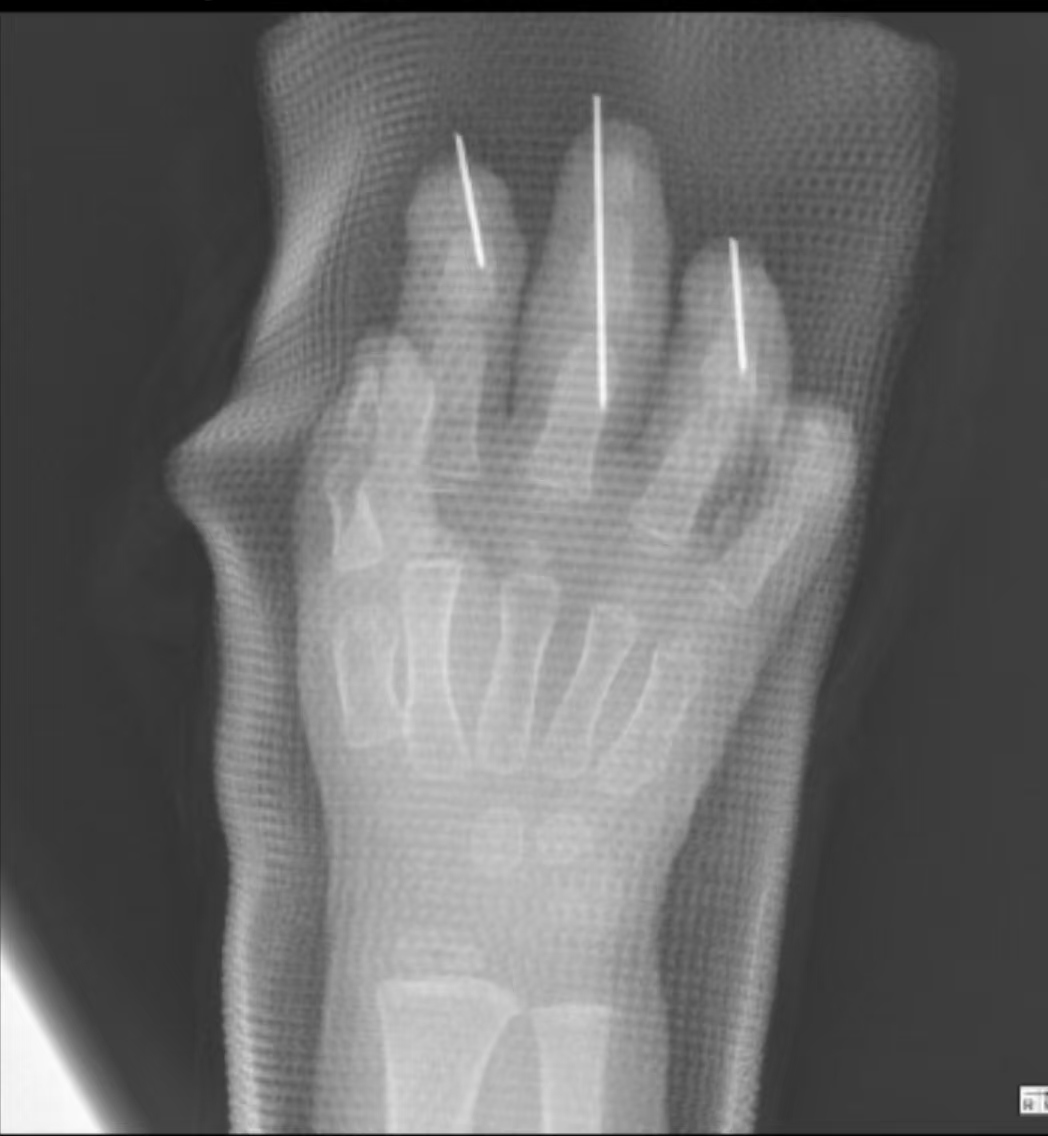

患儿的食指、中指、环指中远端多节段离断。

2月9日下午4点,一位抱着孩子的家长急匆匆地冲进东院急诊科,神色慌张地告诉医生,自己的孩子在玩耍时不慎被三角带绞断手指。接诊的医师发现,患儿的食指、中指、环指中远端多节段离断,创面渗血不止,在为他完成止血、包扎及影像学检查后,将其转入东院手外二科病房。

该患儿手术区域的血管内径不足0.2毫米,细如发丝,再植难度远超成人。术中需在放大25-40倍的高倍显微镜下,用比头发丝还细的显微缝线,在不足1毫米的操作空间中完成血管、神经的精准对接。每一针仅有一次机会,稍有不慎都会导致血管痉挛或栓塞,手术失败。术中,医生发现患儿的手指指动脉严重挫伤,主干血管多处栓塞、断裂,无法直接吻合,面对这一难题,果断采用“静脉移植桥接”技术,从患儿腕部取5厘米浅静脉,重建血运通路,而这无疑再次提升了手术的操作难度。经过6小时的奋战,患儿离断的手指逐渐恢复红润,手术结束。

医生及时为患儿接上断指。